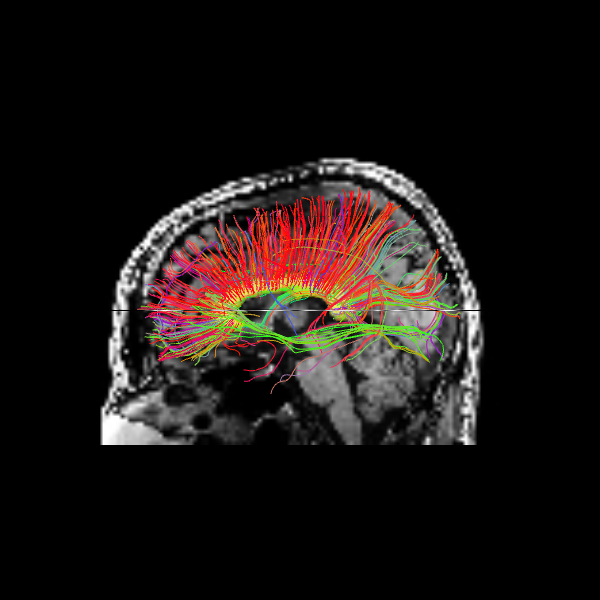

The following alternative visualizations display the corpus callosum streamlines overlaid on T1-weighted anatomical slices (axial at z=35 and sagittal at z=35), with the seed ROI shown as a semi-transparent yellow contour.

# Make display objects

cc_streamlines_actor = actor.line(

streamlines_det, colors=colormap.line_colors(streamlines_det)

)

cc_ROI_actor = actor.contour_from_roi(seed_mask, color=(1.0, 1.0, 0.0), opacity=0.5)

vol_actor = actor.slicer(t1_data)

vol_actor.display(x=40) # sagittal slice

vol_actor2 = vol_actor.copy()

vol_actor2.display(z=35) # axial slice

# Add display objects to canvas

scene = window.Scene()

scene.add(vol_actor)

scene.add(vol_actor2)

scene.add(cc_streamlines_actor)

scene.add(cc_ROI_actor)

# Save figure

window.record(

scene=scene, n_frames=1, out_path="corpuscallosum_axial.png", size=(600, 600)

Image("corpuscallosum_axial.png")

The sagittal view illustrates these interhemispheric pathways connecting the two hemispheres.

scene.set_camera(position=[-1, 0, 0], focal_point=[0, 0, 0], view_up=[0, 0, 1])

scene=scene, n_frames=1, out_path="corpuscallosum_sagittal.png", size=(600, 600)

Image("corpuscallosum_sagittal.png")